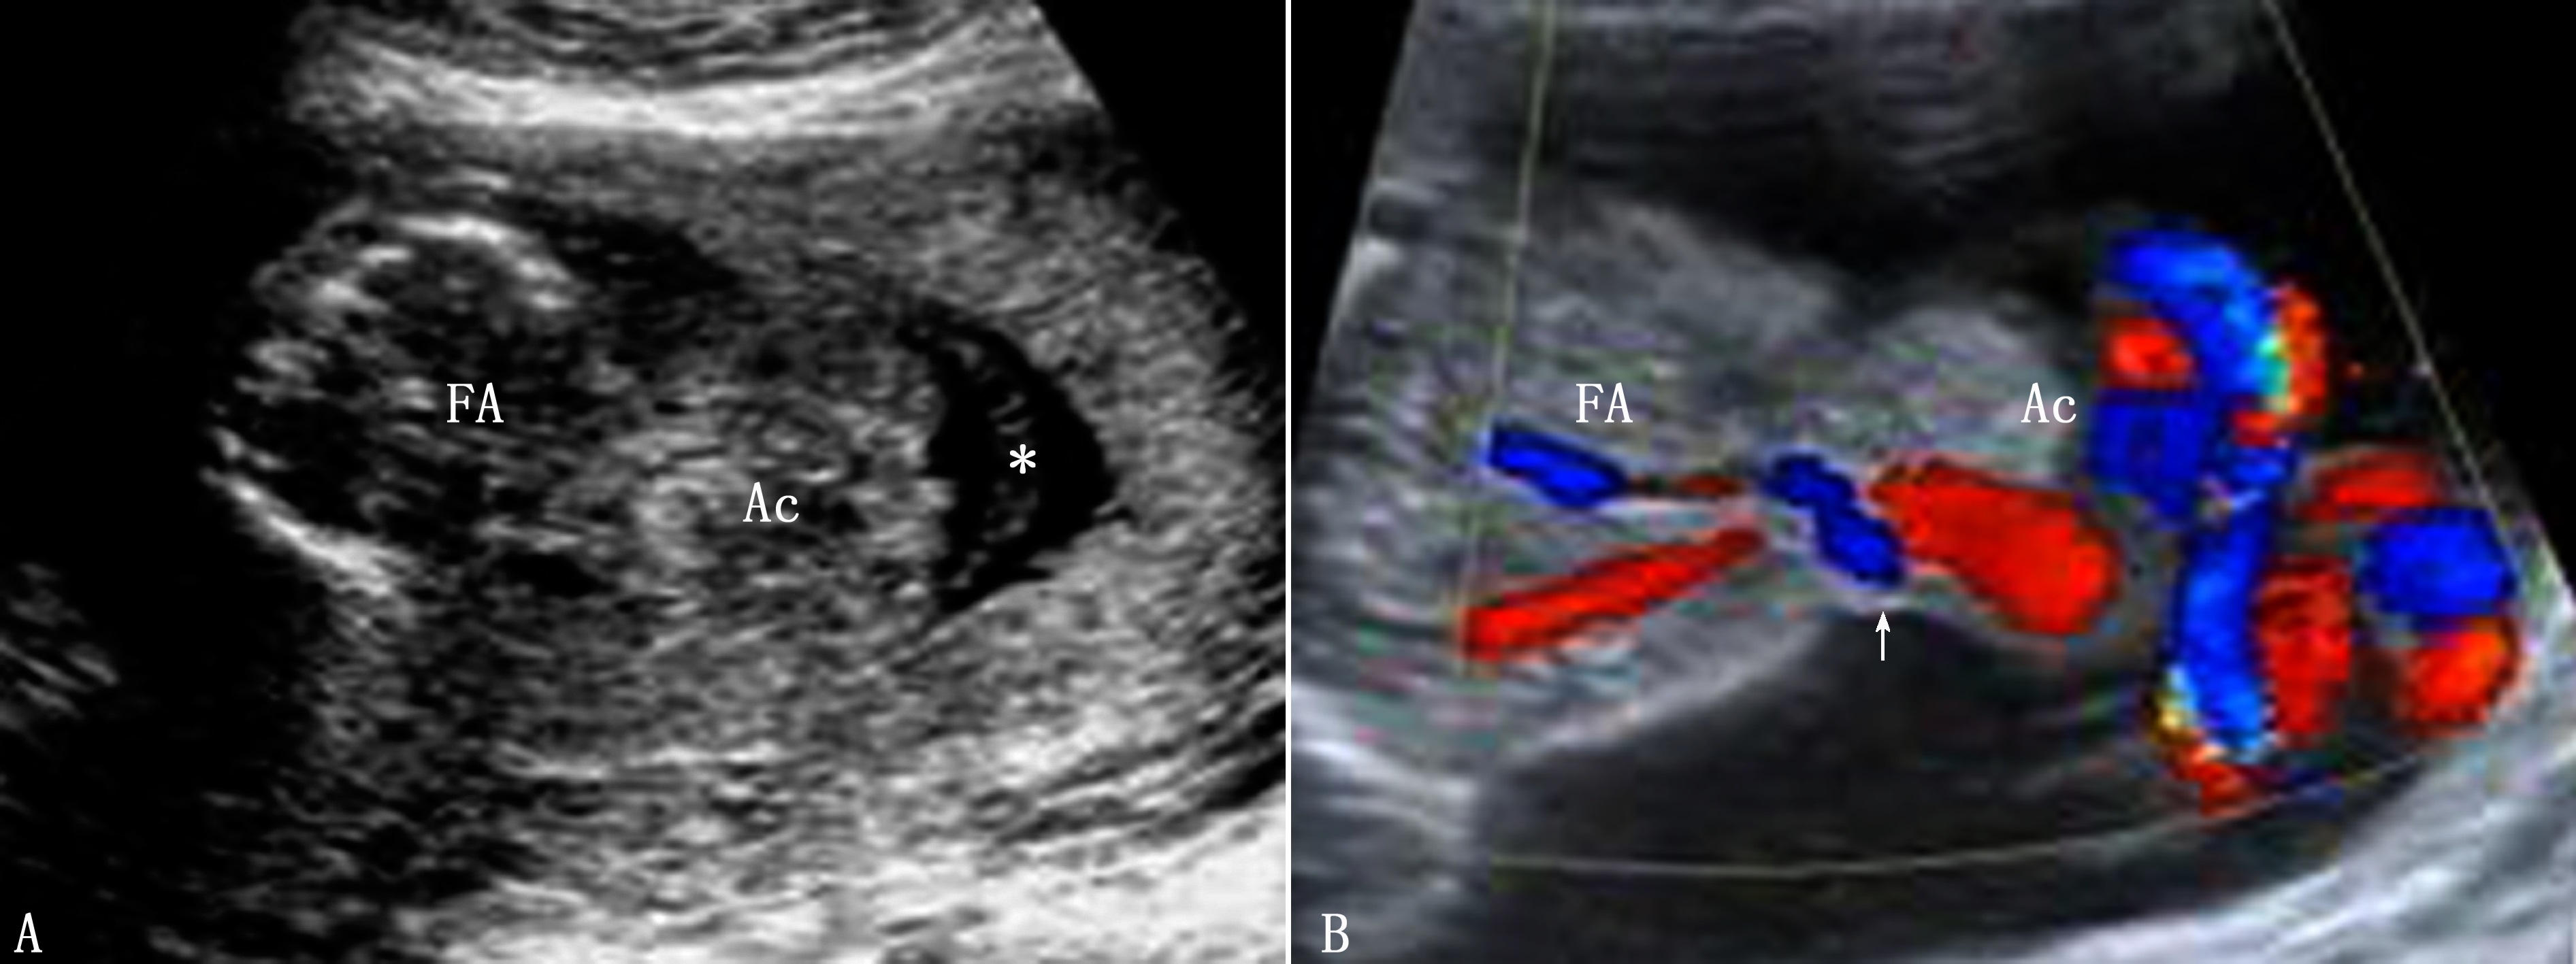

超声诊断:前腹壁中线处回声中断、缺损。脐根部见一向外膨出的包块,包块表面有一层菲薄的强回声膜覆盖。表面见脐带根部,彩色多普勒显像可显示脐带与包块的关系(图1)。内容物可因缺损的大小不同,缺损小时,仅有肠管;当缺损较大时,可有肝脾等内容物。小的脐膨出与染色体异常有关,而含有肝脏的较大脐膨出染色体异常的发生率低。

图1 孕17周胎儿脐膨出(Ac)声像图